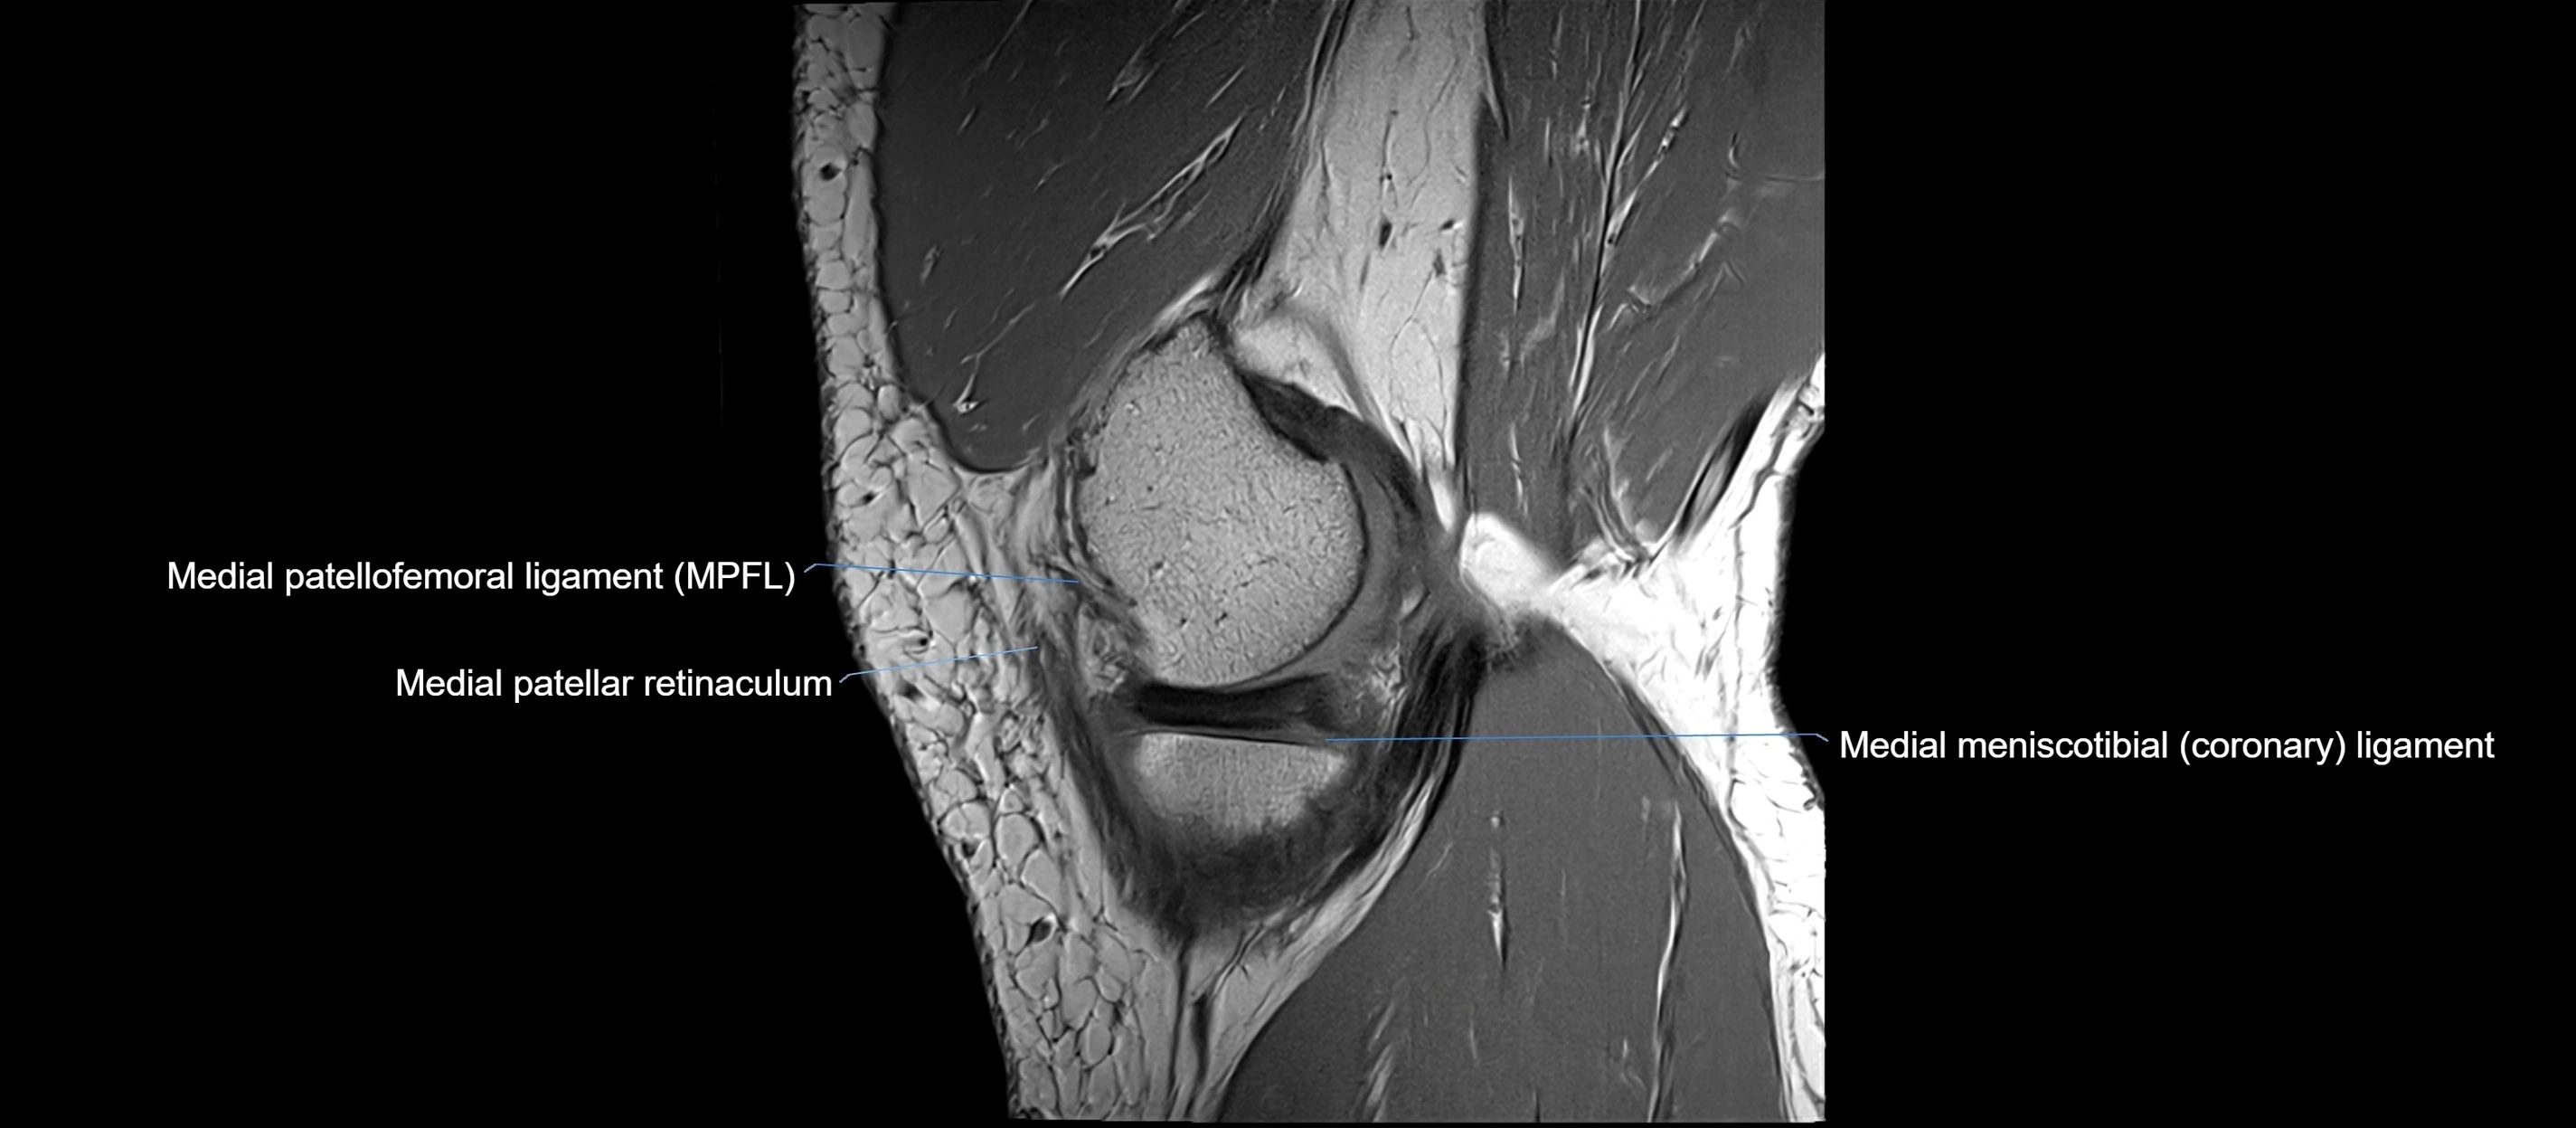

MRI images

image